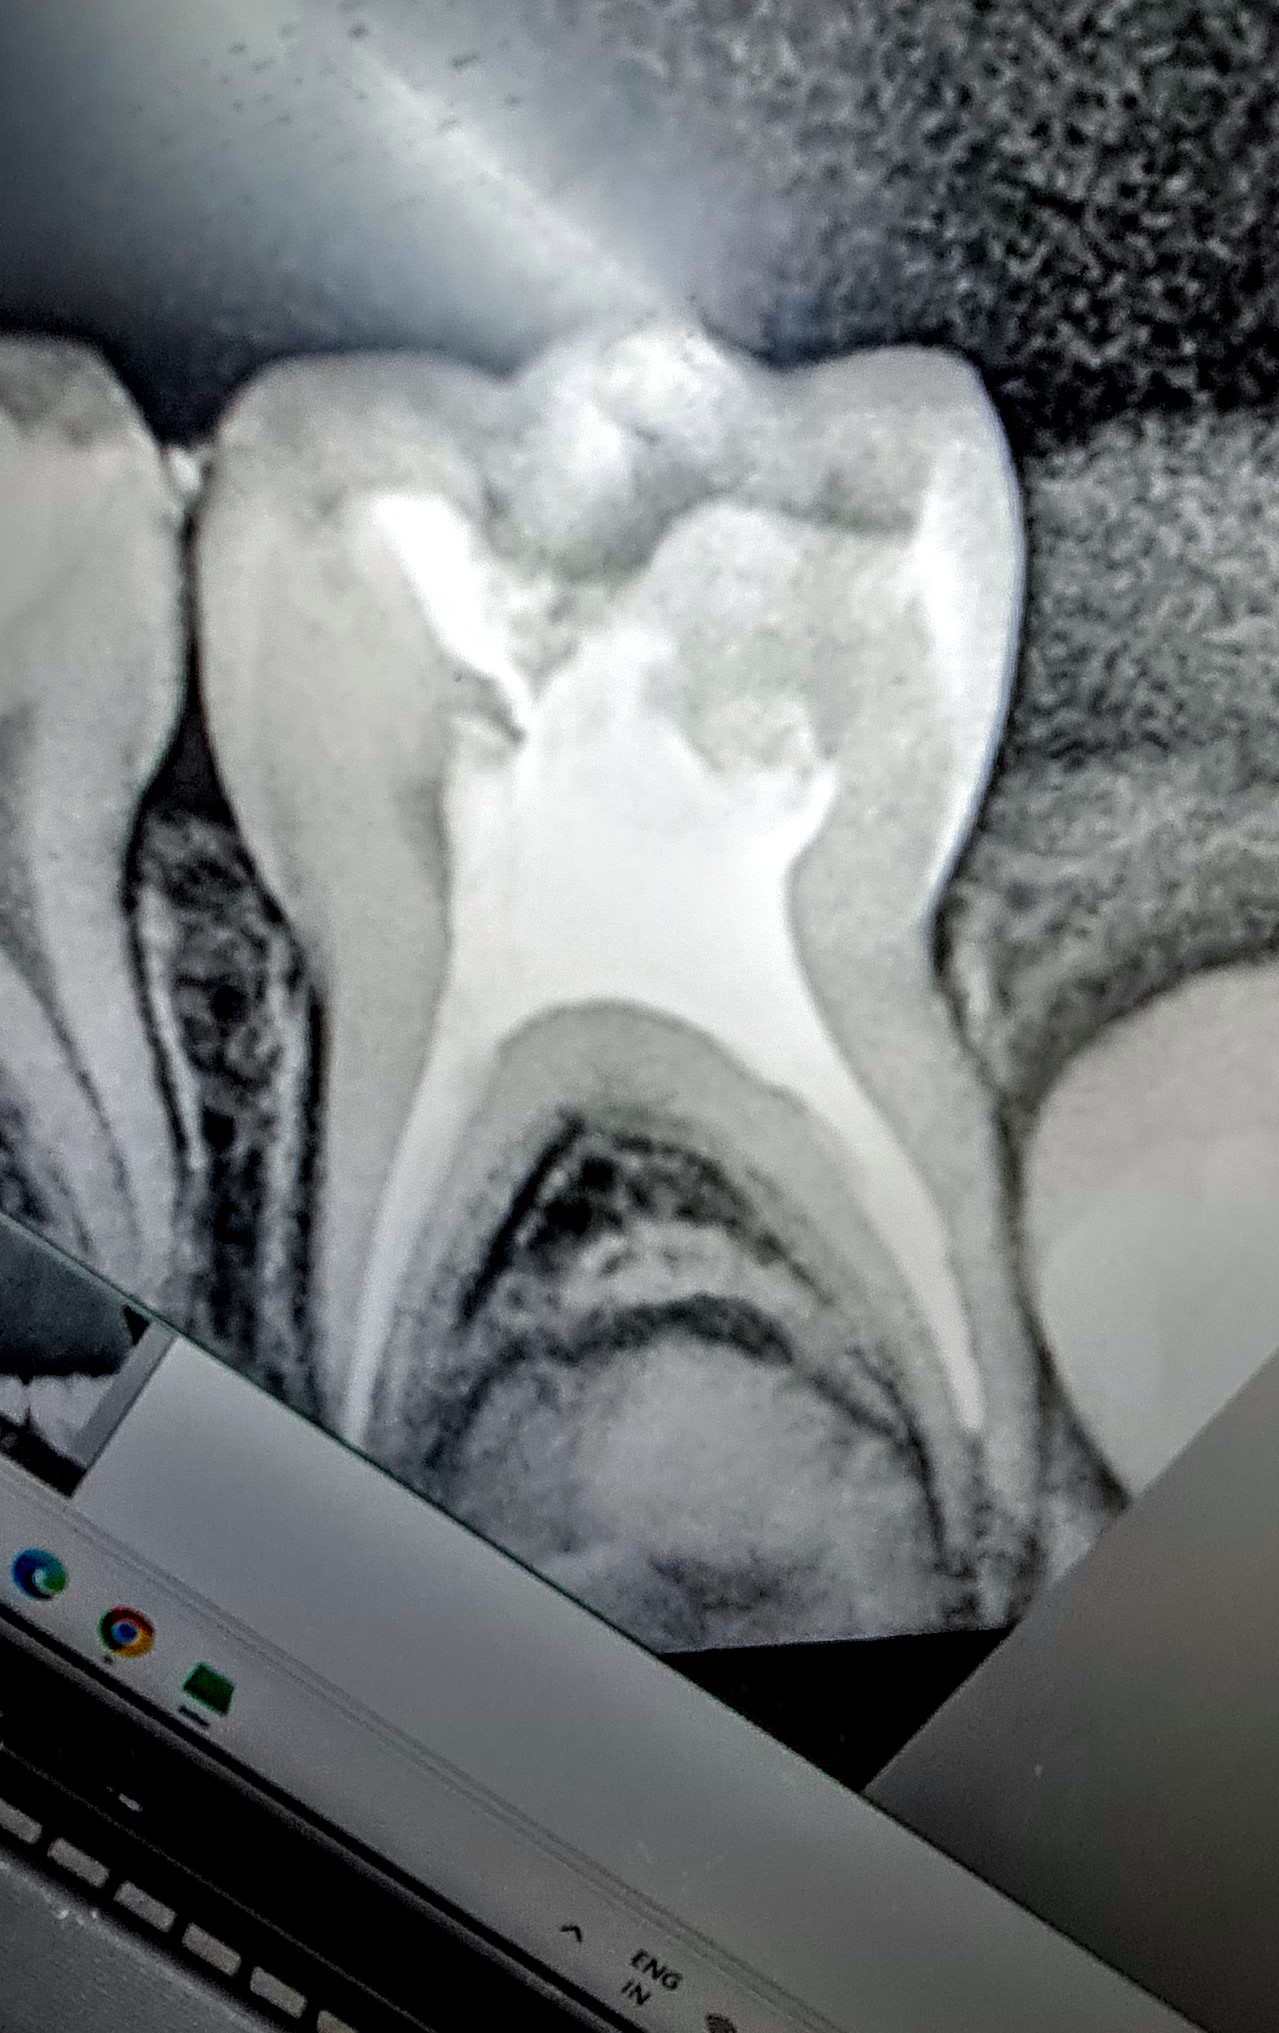

Dental Pain in Kids? Is your kid suffering from Toothache? Dental Pain in Kids can be due to cavities which can occur due to multiple causes. It is important for the kid to get the Best Dental Treatment! The treatment is needed to prevent any infection which may even damage the permanent teeth present beneath it! To provide your kids withThe Best Dental Treatment , visit Smiles For All Dental Clinic , The Best Dental Clinic in Rohini Sector 11! We have The Best Kids Dentist in Rohini Sector 11 who will make sure to provide your kid a fun filled dental treatment!